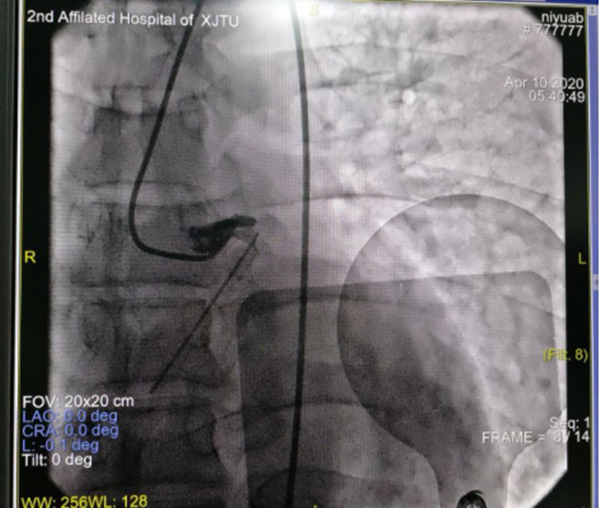

4月10日的凌晨2点钟,熟睡中的韩先生突然惊醒,心前区剧烈的疼痛伴随着难耐的胸闷气短,让正处壮年既往十分坚强的他产生了濒死的恐惧感,赶来的家属惊慌地拨打了120急救电话,将他送到了整合心血管病院。入院当时便出现了恶性心律失常、意识丧失,心内科薛嘉虹副主任医师就地组织抢救,心电图提示冠脉左主干病变,这在冠脉病变中属于非常严重的一种类型,随时有猝死风险,经与家属迅速有效沟通后紧急转运至导管室行冠脉介入治疗,考虑病情危重,心内科联系心外科协助抢救,心外科王春亚副主任医师、牟明超医师立即行气管插管接呼吸机辅助呼吸,并进行循环监测,为手术保驾护航。心内科薛嘉虹副主任医师、王新宏副主任医师娴熟操作,迅速植入主动脉内球囊反搏(IABP)装置辅助循环后行冠脉造影+冠脉支架植入术,手术历时1小时余顺利结束,术后的他仍意识模糊、四肢湿冷、血压难以维持、反复出现恶性心律失常,考虑心脏泵功能衰竭心源性休克,病情极其凶险,遂转入重症监护设施相对更加完备的心外科监护室,由王春亚副主任医师、王宇医师所在心脏重症团队继续监护治疗。冠脉造影术中发现患者冠脉左主干自起始部完全堵塞,心脏前壁运动幅度低,结合实验室检查心脏损伤指标测值超过可测定的上限等化验结果,提示心肌梗死面积大,近期可能突发乳头肌断裂、室间隔穿孔、左室游离壁破裂等紧急且危及生命的心脏机械并发症,病情比想象中的更加危重,这是一场与死神的生死较量,在全力抢救的同时,心外科全体医护人员共同在心里为他祈福。

冠脉造影:左主干起始段闭塞